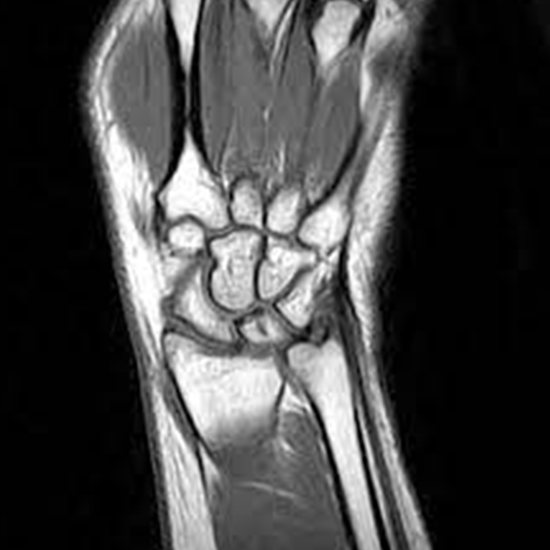

mri screening of right wrist

MRI Screening of the Right Wrist is an imaging of the right wrist joint. It is recommended to diagnose and determine the wrist’s anatomy and problems associated with the right wrist and its adjoining structures including the bones, tendons, ligaments, muscles, and blood vessels. The compression of nerves underneath the right wrist causes the problems such as carpal tunnel syndrome, and damage to fingers. It helps in diagnosing major and minor injuries sprain, repetitive stress injury also arthritis.